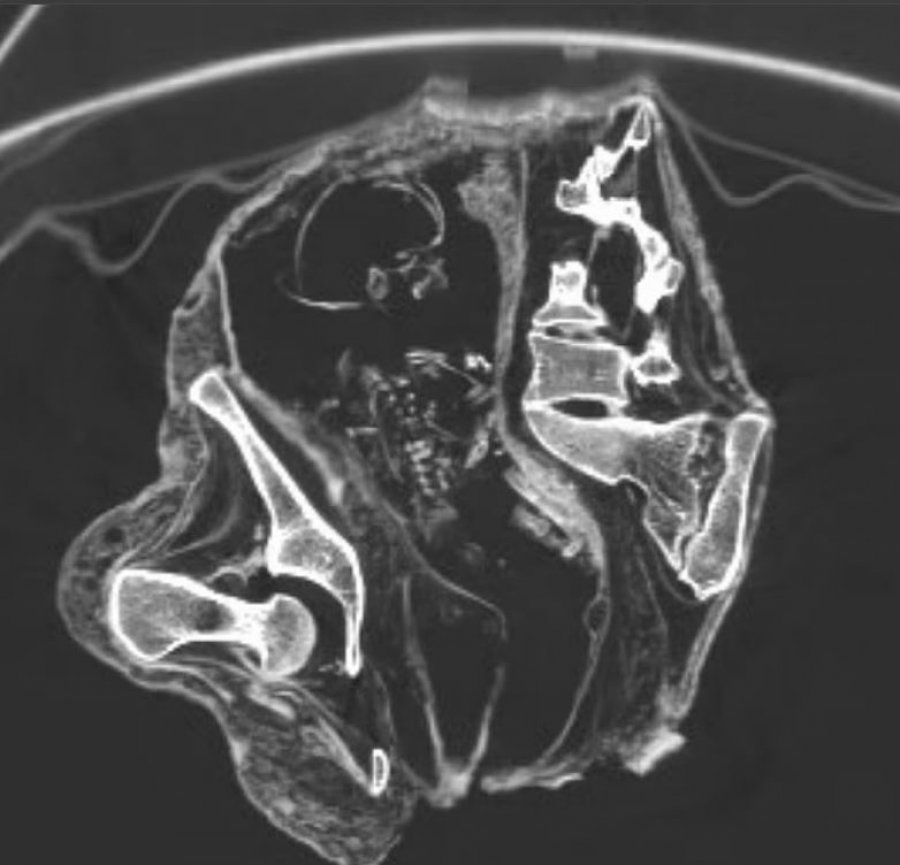

Skanimet CT kapën ‘fetusin’ të shtrirë përmbys, me kokën poshtë pranë zonës së barkut dhe gjoksin me krahët më afër rajonit të legenit.

Shkencëtarët sugjeruan se kockat e saj ishin ende të buta, sapo kishin filluar të ngurtësoheshin, kur Montserrat vdiq, duke lënë pjesë të shtyllës kurrizore dhe brinjëve të paafta të bashkoheshin së bashku.

Ata përcaktuan moshën e ‘fetusit’ bazuar në madhësinë e femurit të tij, 43 milimetra të gjatë, e cila përdoret për të vlerësuar moshën gestacionale në ultratingujt prenatalë, duke sugjeruar se ishte më pak se 30 javë.

Ndërsa indi tkurrej, muskujt në mitër ruajtën formën e tyre të përgjithshme, por kafka e butë dhe e pazhvilluar dhe kockat e fytyrës, zhvendoseshin.

Kur shkencëtarët rindërtuan në mënyrë digjitale fetusin, ata zbuluan se fytyra e tij ishte kthyer mbrapsht.

Në kohën e vdekjes, kockat e fetusit ishin ende të buta dhe jo plotësisht të formuara, duke i bërë ato më të ndjeshme ndaj shtrembërimit gjatë mumifikimit, sipas studiuesve.

Shkencëtarët thanë se kjo shpjegon pse shtylla kurrizore dhe brinjët, duken të thyera ose të çrregullta në skanime.

Disa pjesë të kockave, veçanërisht pllakat e rritjes në skajet, nuk janë fare të dukshme në imazhet CT.